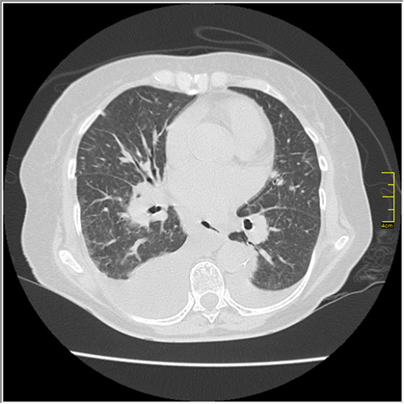

La paciente es ingresada a la Unidad de Cuidados Intermedios donde le practican una TAC de tórax de alta definición (Figura 4).

Figura 4: Tomografía de tórax de alta resolución. Derrame pleural bilateral asociado a atelectasia, imágenes de patrón en vidrio esmerilado e imágenes parcheadas en ambos campos pulmonares.